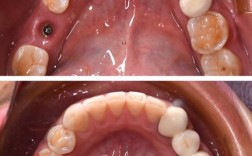

舌侧矫治与隐形矫治附件粘结

舌侧矫治因托槽位于舌侧,操作空间狭小且隔湿难度大,Ortho Bond化学固化粘结剂无需光照,无需严格隔湿即可实现稳定粘结;隐形矫治附件(如附件、小钩)体积小、粘结精度要求高,Ortho Flow流体树脂的低粘稠度可精确填充附件与牙面间隙,粘结强度达15MPa以上,避免附件脱落影响矫治进程。